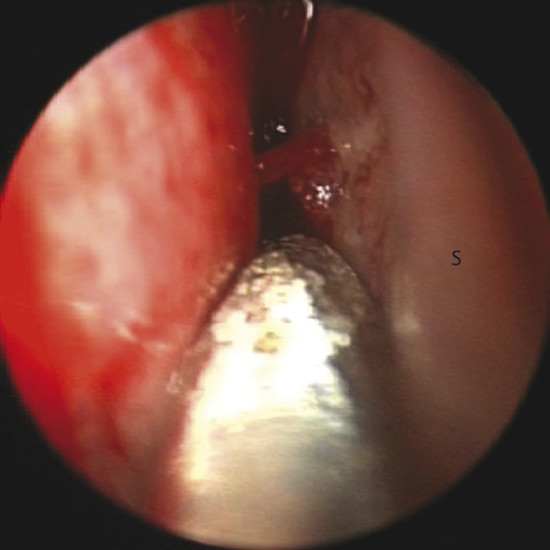

Bleeding can be seen originating from a septal branch of the AEA, showing a close anatomic relation with the axilla of the middle turbinate (Fig. 13‑4). It is extremely important to consider this anatomical relation during harvesting the flap.